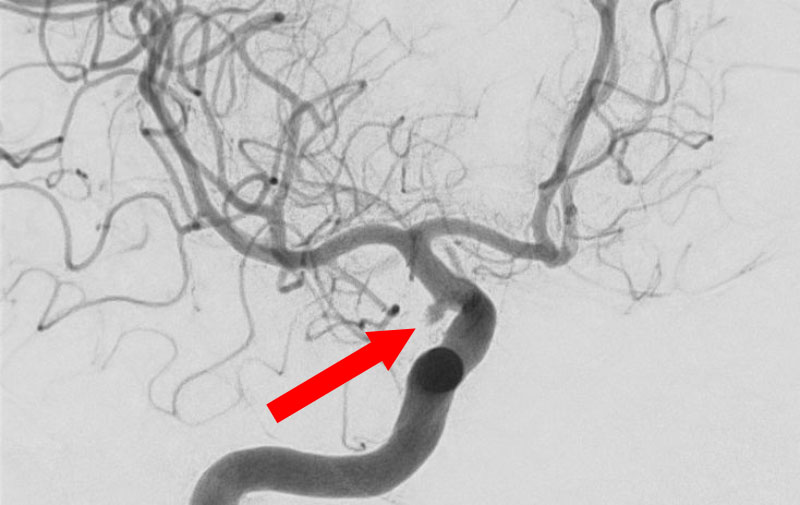

No.1595 手術前